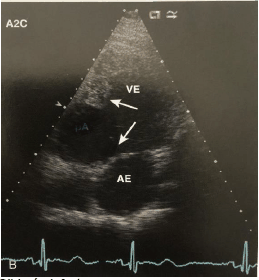

Um ecocardiografista foi chamado de urgência para avaliar um paciente de 70 anos, do sexo masculino, que apresentou no décimo segundo dia de evolução de infarto agudo do miocárdio, um quadro de insuficiência cardíaca congestiva. Segue a imagem adquirida durante o exame ecocardiográfico.

Assinale a alternativa que apresenta a que complicação a imagem abaixo se refere.